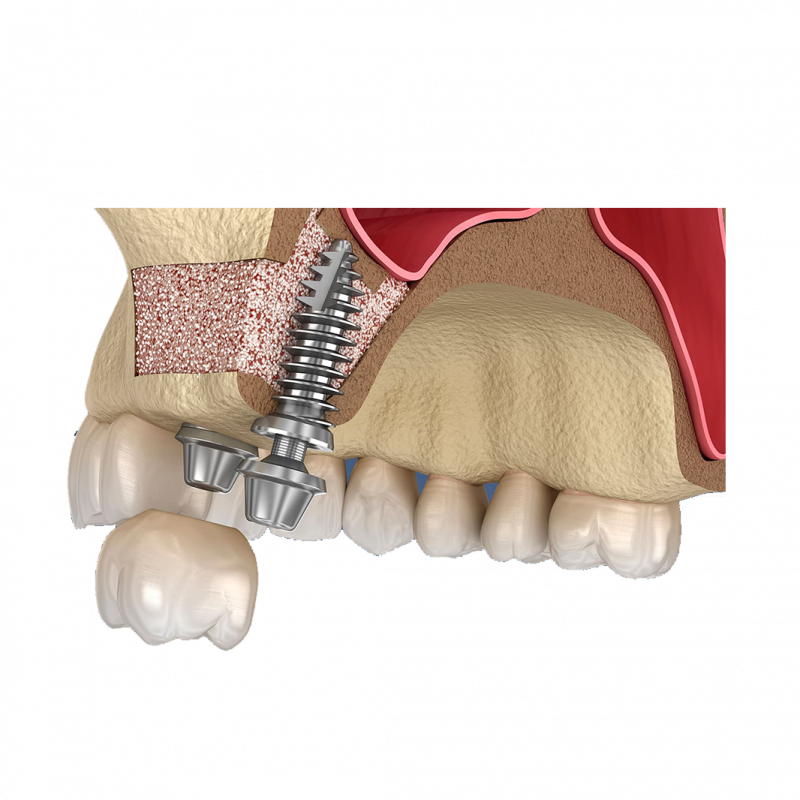

Oluşan bu yeni boşluğa (çene kemiği ile sinüs zarı arasındaki boşluk) kemik materyali (kemik grefti) yerleştirilir ve kemik materyalini yerinde tutmak için üstüne genellikle bir kollajen membran yerleştirilir. Diş eti dokusu daha sonra dikişlerle kapatılır.

Sinüs Lifting işleminde kullanılan biomateryalin türüne bağlı olarak, kemik greftinin çene kemiği ile bütünleşmesi genellikle dört ila altı ay sürer.

Sinüs Lifting yapıldığı seansda ,implant yapılabilmesi için yeterli kalınlık ve kalitede kemik mevcut ise aynı anda implant yapılabilir.